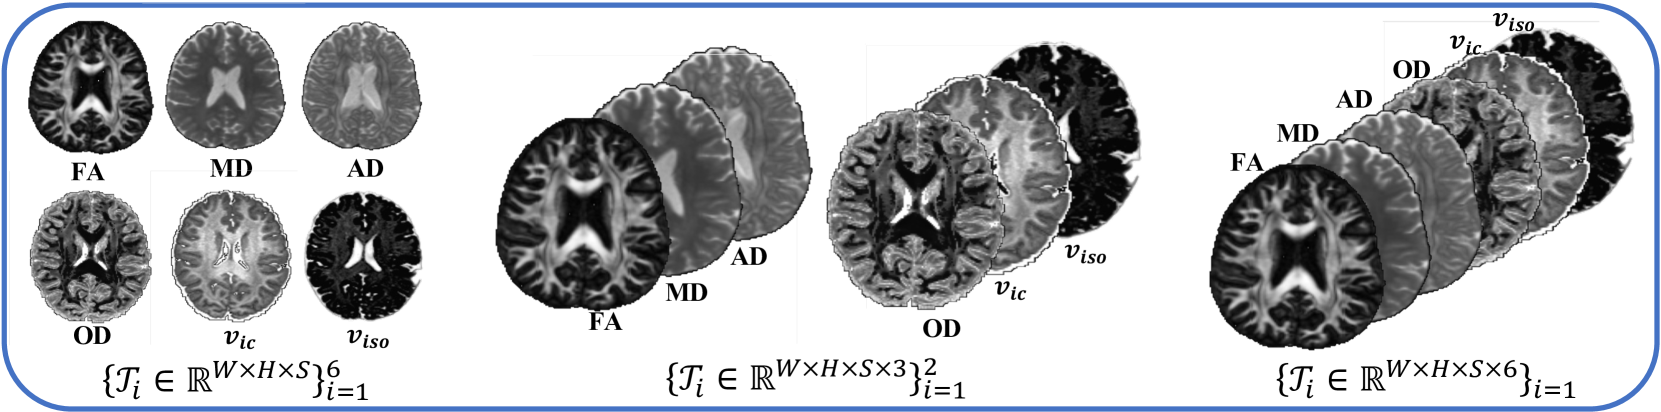

Leveraging multiple microstructural features from different diffusion models contributes to a more comprehensive understanding of brain microstructure. As presented in Figure 1, multiple microstructural parameters from different diffusion models rely on the same biological tissue, sharing the same anatomical and diffusion information, thus demonstrating high correlation. However, despite the promising achievements, the efficiency and accuracy of multi-parametric estimations remain limited as previous deep learning-based studies have primarily focused on estimating multi-parametric maps individually using isolated signal modeling. Although some research has employed multi-parametric learning [25, 33, 34, 35], they tend to directly output multiple parameters without considering the correlation among parameters.

5.2 Discussion on the dimensions of the multi-parameter Tensor

The high dimensionality of multiple parameters allows for various methods to decompose this tensor. This section explores the impact of tensor dimensions on the proposed method. We conducted a detailed study on three tensor dimensions presented in Fig. 6: decomposing the six parameters as individual tensors, grouping the DTI and NODDI parameters into two sets, and merging all six parameters for decomposition. The findings in Fig. 7 suggest that, when considering 18 DWIs (with uniform 6 diffusion directions per shell at b-values of 1000, 2000, and 3000 ), the best performance is achieved when merging the six parameters, highlighting the effectiveness of the DeepMpMRI in leveraging the correlations between multiple parameters and the redundancy of high-dimensional data.